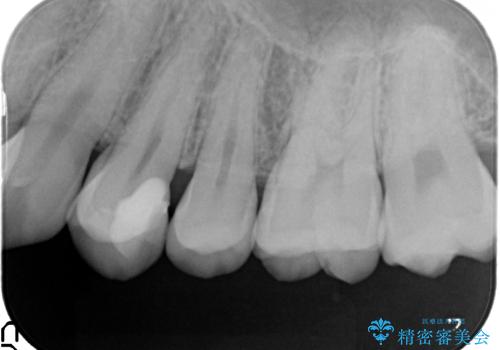

気づかないうちに大きな虫歯が 神経を保存し、セラミックで修復

- 神経を温存し、セラミックインレーによる修復をおこなった。

深い虫歯があった場合、たとえ神経を温存できたとしても長期的には痛みが出てきたり、神経がいつの間にか失活(正常な反応を失う)してしまったりするリスクはあります。

安易に神経を取り除くべきではありませんが、神経を保存するのであればそのようなリスクをよく理解していただく必要があります。

詰め物の種類:e.max press